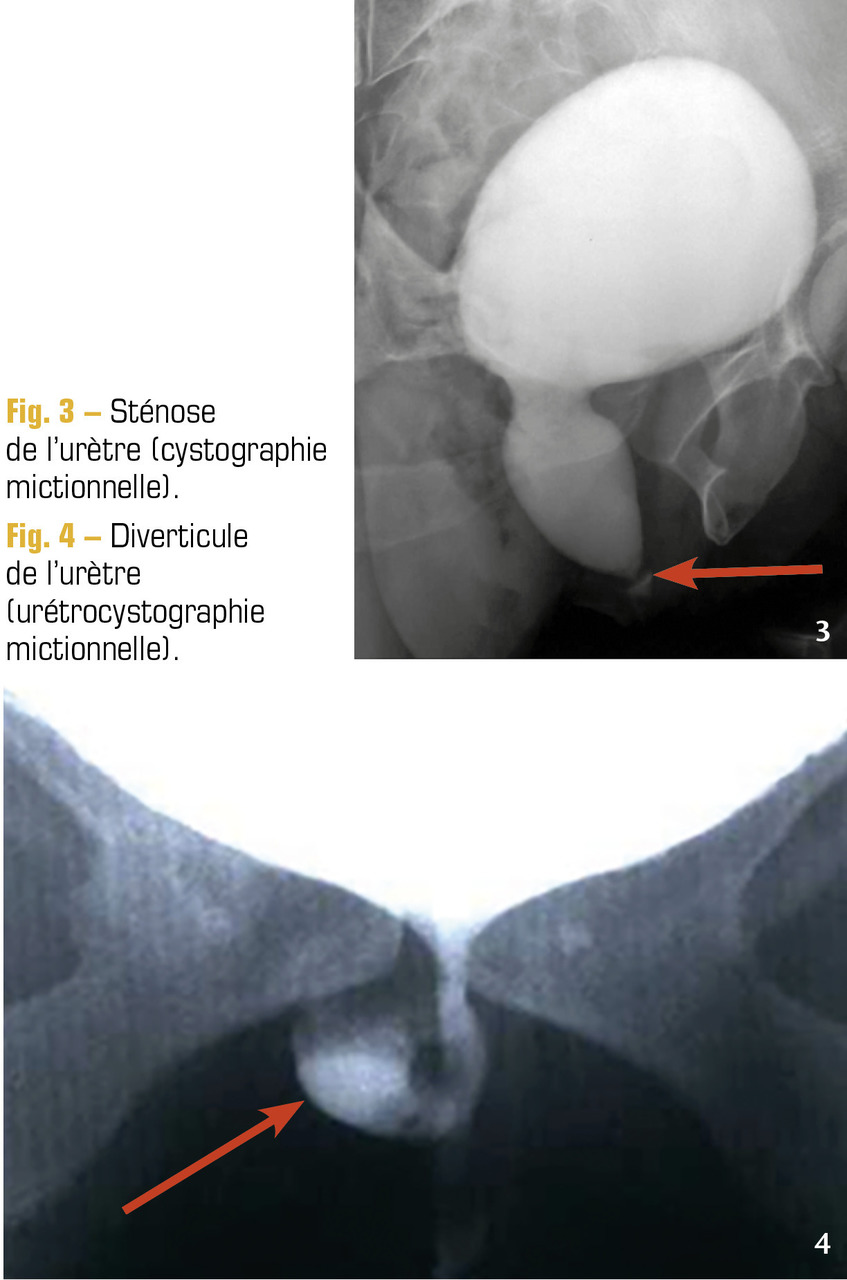

Si sténose de l’urètre (fig. 3), rare chez la femme : urétrotomie interne.

Un diverticule sous-urétral (tuméfaction de la paroi vaginale antérieure), diagnostiqué par une échographie transvaginale et une cystographie mictionnelle (fig. 4) doit être enlevé sous anesthésie générale.